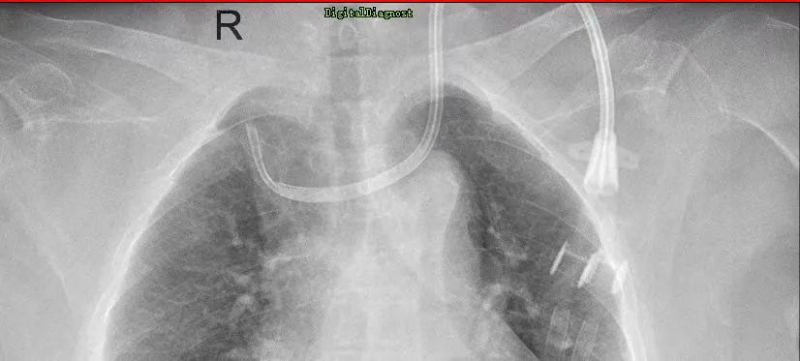

不久前,一位来自河源的患者到惠州市中心人民医院中文博彩平台分院(中文博彩平台人民医院)肾内科纠正导管位,这位日常是在当地的医院进行腹透导管,但总有不适感产生,听闻惠州市中心人民医院中文博彩平台分院(中文博彩平台人民医院)肾内科导管技术优秀,慕名场来求医。这位病人在当地医院进行血液透析,但导管流量不足,无法常见透析,到了惠州市中心人民医院中文博彩平台分院(中文博彩平台人民医院)就医以后,肾内科主任吴勇对他进行了全面的检查,发现该病人体内的导管已经像项链一般绕脖一圈,需要立马纠正。吴勇马上联系了惠州市中心人民医院的手足外科专家进行会诊,经讨论后对患者进行了球囊扩张术,并重新置入新的导管,术后患者透析顺利,返回当地后也能继续顺利透析。该病人对惠州市中心人民医院中文博彩平台分院(中文博彩平台人民医院)微创置管导管技术表示了高度的认可,并定期回院复诊。

肾内科从2018年分科建立以来,逐步发展壮大。在新一代学科带头人吴勇的带领下,学科克服了人才引留困难、临床科研基础薄弱、信息相对闭塞等难题,全科上下积极进取、砥砺前行,在诊疗技术水平、医疗服务能力、科研教学能力、人才培养及学科影响力等方面取得了重大突破。如前期需要在手术室剖腹进行的腹透置管手术,术后创口大,手术时间久等一系列缺陷,存在许多弊病,吴勇首先对其进行针对指导改良,微创化、轻量化,从经皮穿刺置管术转变到现在的改良型腹腔镜下腹透置管术,患者术后半日即可下床自行活动,不会有明显痛苦。科室还开展了上腔静脉狭窄球囊扩张术,解决血液透析长期导管带来的副作用。

2. 血管通路手术、DSA下的疑难置管,上腔静脉造影+球囊扩张+置管术(静脉置管、动静脉内瘘、血液透析长期静脉导管),彩超引导下经皮静脉球囊扩张术,是血液透析病人血管通路狭窄治疗的利器,可以减少病人痛苦,最大的可能保护病人的血管。